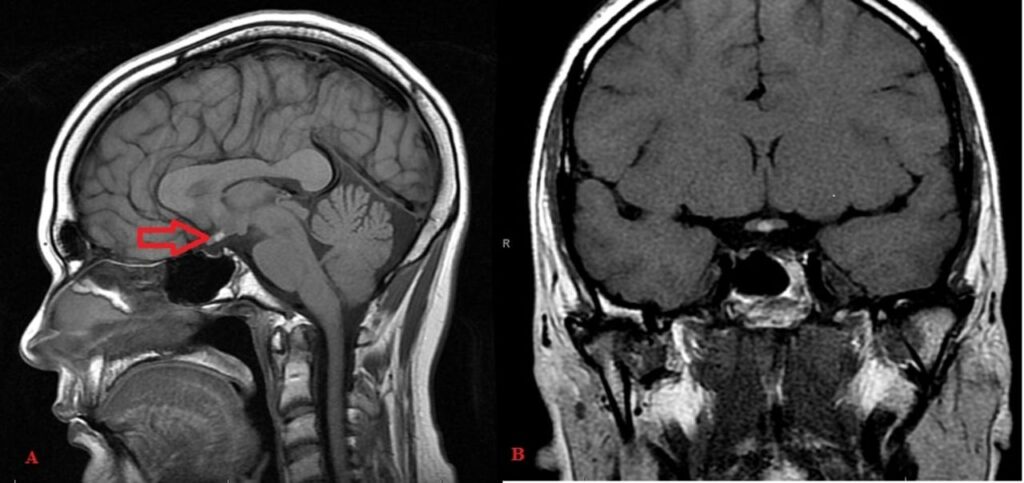

- MRI Scan